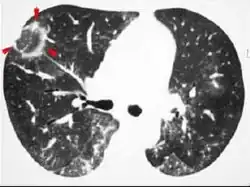

Plain chest radiography shows normal lung volumes, with characteristic patchy unilateral or bilateral consolidation. Small nodular opacities occur in up to 50% of patients and large nodules in 15%. On high resolution computed tomography, airspace consolidation with air bronchograms is present in more than 90% of patients, often with a lower zone predominance. A subpleural or peribronchiolar distribution is noted in up to 50% of patients. Ground glass appearance or hazy opacities associated with the consolidation are detected in most patients.

Unusual presentations of organizing pneumonia

While patchy bilateral disease is typical, there are unusual variants of organizing pneumonia where it may appear as multiple nodules or masses. One rare presentation, focal organizing pneumonia, may be indistinguishable from lung cancer based on imaging alone, requiring biopsy or surgical resection to make the diagnosis.[20]